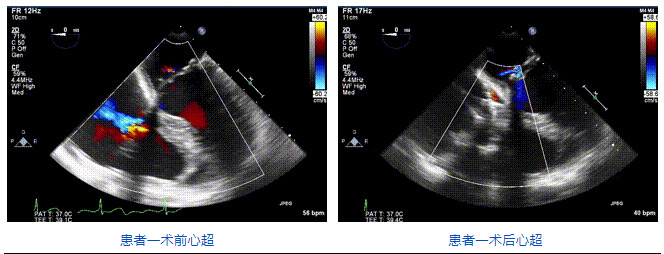

2021年12月24日,復(fù)旦大學(xué)附屬中山醫(yī)院葛均波院士團(tuán)隊(duì)成功應(yīng)用LuX-Valve Plus為一例極重度三尖瓣反流(TR)合并房顫、房缺的患者完成了經(jīng)血管三尖瓣置換術(shù),這是在前基礎(chǔ)上,本周完成的第三例經(jīng)血管三尖瓣置換手術(shù),葛均波院士、周達(dá)新教授等與心外科魏來教授、賴顥教授,心超室的潘翠珍教授、李偉教授及麻醉科的郭克芳教授共同完成了本周手術(shù),均獲得圓滿成功!患者術(shù)后超聲顯示無TR,臨床癥狀明顯改善。本周手術(shù)的成功也為L(zhǎng)uX-Valve Plus救治性臨床研究添上了濃墨重彩的一筆。

三例患者入院后,葛均波院士團(tuán)隊(duì)周達(dá)新教授、潘文志教授、張?jiān)床┦俊㈥惿┦考靶某业呐舜湔浣淌?、李偉教授?duì)患者的情況進(jìn)行詳細(xì)評(píng)估和討論,最終決定為三例患者選擇LuX-Valve Plus40mm、50mm和50mm型號(hào)的瓣膜進(jìn)行手術(shù)治療。手術(shù)后即刻拔除氣管插管,術(shù)后患者三尖瓣反流癥狀得到顯著改善,復(fù)查心超結(jié)果顯示人工三尖瓣瓣膜支架固定穩(wěn)定,瓣葉關(guān)閉形態(tài)未見異常,未見明顯反流。